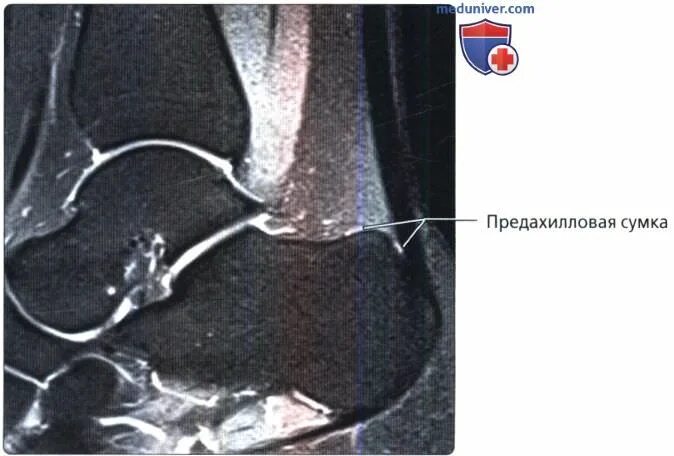

Мрт ахиллового сухожилия